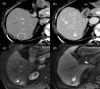

MRI is widely used in clinical practice for detecting liver diseases. Since the introduction of gadoxetic acid, MRI has become the most effective modality for the detection and characterization of focal liver lesions. According to previous meta-analyses, the area under the receiver operating characteristic curve (AUROC) was 0.97-0.99 for the diagnosis of small hepatocellular carcinoma (≥ 2 cm) by gadoxetic-acid-enhanced MRI. Moreover, the AUROC for the diagnosis of colorectal liver metastases was significantly high (0.98). Despite gadoxetic acid's drawbacks, its clinical utility outweighs them, making it the contrast agent of choice in routine liver MRIs. Moreover, clinically, liver MRI has become more prevalent for a quantitative assessment. Liver fibrosis can be evaluated using MR elastography; whereas, hepatic steatosis and iron overload can be evaluated using proton density fat fraction, with high accuracy and reproducibility. This article reviewed the usefulness of liver MRI, which can be a comprehensive imaging modality in clinical practice.